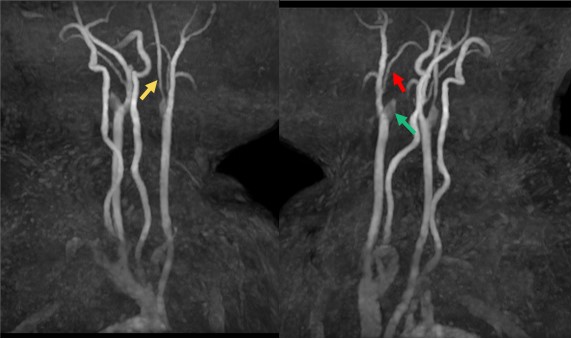

患者头颅MRA显示右侧颈内动脉及大脑中动脉完全闭塞,左侧颈内动脉狭窄,大脑中动脉未显影。立即往下扫描了颈部 MRA,颈部MRA显示右侧颈内动脉闭塞(绿箭),并在右侧颈外动脉多出了一个分支延伸至颅内(红箭),左侧颈内管腔狭窄(黄箭)。如此大面积的血管未显影,DWI上却未见新发病灶,病因是什么呢?

3D ASL为我们解答了为何患者血管大面积不显影,DWI上没有新发病灶,综合PLD=1.5s和2.5s来看患者虽然双侧大脑中动脉和大脑前动脉闭塞,但有灌注代偿,并未影响大脑供血;右侧顶枕叶呈现高灌,也印证了在TOF MRA上看到的右侧枕叶粗大的侧枝血管有代偿供血。到这一步基本解答我们的疑问,或许我们还需要一些直接的征象来证明我们的判断。SilenZ MRA(静音血管)也许能让我们看到更多的信息:

大范围基于3D ASL和ZTE的SilenZ MRA显示右侧颈外出现一支大的侧枝血管,供应右侧大脑,左侧颈内颅内段末端出现小的侧枝血管,且能看到Willis环周围许多细小的血管。

结合前面3D ASL和SilenZ MRA的征象,能想到烟雾病了,后询问得知患者有烟雾病家族史,遂入院进行相应治疗。